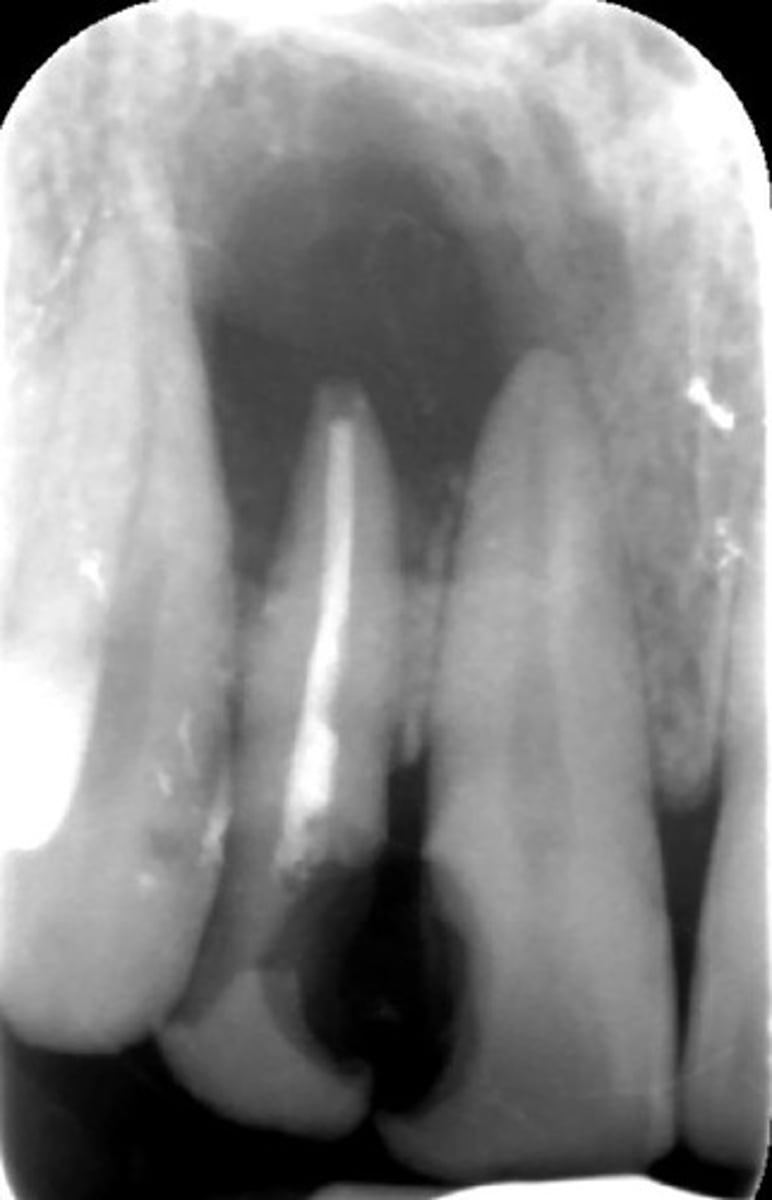

how would you describe this lesion? (not the giant cavity btw)

A. defined, corticated, periapical radiolucency causing loss of lamina dura and PDL space on #6-7

B. defined, non-corticated, periapical radiolucency causing loss of lamina dura and PDL space on #6-7

C. ill-defined, circular radiolucency located above tooth #7

D. well-defined, corticated, radiopacity

- Also note epicenter located above apex # 7 which has large dental caries.

What category would this lesion be part of?

Inflammation/benign

all of the following could be a differential diagnosis for the following lesion EXCEPT?

A. radicular cyst

B. Periapical granuloma

C. apical rarefying osteitis

D. renal osteodystrophy

what category would this lesion be classified into?

inflammatory/benign cystic